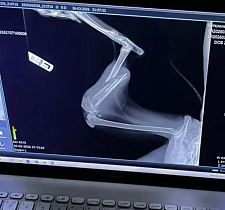

«Специалисты пришли к выводу, что рысь некоторое время назад стала жертвой ДТП, - рассказала директор «Легенды» Наталия Иванова. - У нее сломаны резцы, отсутствует клык, травма глаза, переломы передней и задней лап».

Кроме набора веса, рыси предстоит еще несколько операций в «Госпитале дикой природы». После этого животное вернется в «Легенду» - животное не предназначено к выпуску, поскольку полная реабилитация, в том числе полное восстановление зрения, уже невозможно.